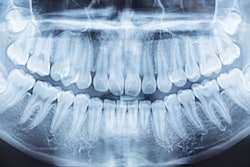

A new tool the size of a toothpick may be capable of detecting tooth decay before it shows up on an x-ray and could be the latest tool in the fight against cavities, according to an article recently published by Tufts University.